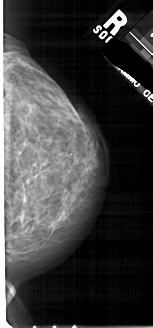

A_1724_1.RIGHT_MLO

LEFT_MLO LINES 5491 PIXELS_PER_LINE 2806 BITS_PER_PIXEL 12 RESOLUTION 43.5 OVERLAY